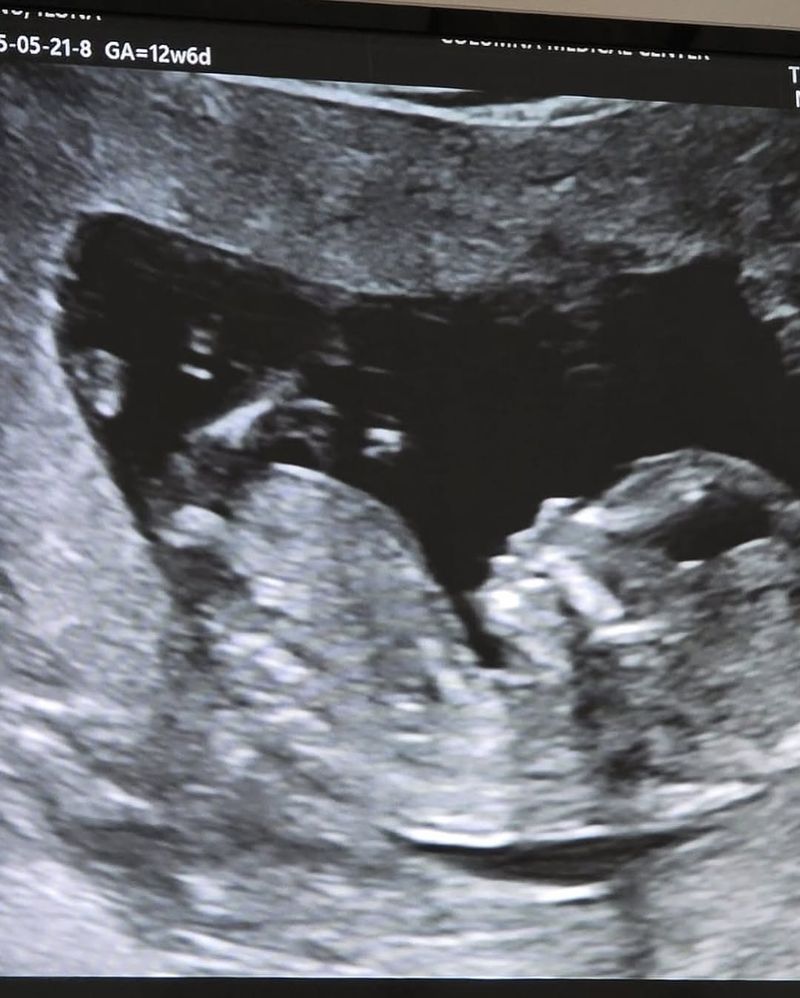

Minunata veste a fost făcută prin intermediul rețelelor de socializare, în urmă cu doar câteva momente. Ilona Brezoianu a postat o poză cu ecografia copilului. De asemenea, în stilul caracteristic, a postat un mesaj emoționant, dar în același timp și amuzant.

Mai precis, vedeta a spus că atât ea, cât și soțul său au nasurile mari, motiv pentru care, cel mai probabil, va aduce pe lume un copil cu aceeași trăsătură fizică. Totuși, aceasta a punctat că amândoi sunt extrem de bucuroși și așteaptă cu nerăbdare momentul în care își vor strânge copilul în brațe pentru prima dată. Urmează un nou capitol important din viețile lor.„Eu și Andrei avem nasurile mari și o să facem un copil tot cu nasul mare. Până una alta e foarte drăguț și noi suntem mega fericiți! V-am pus și o poză cu el ca să mă credeți pe cuvânt. Acum puteți să vă continuați treburile”, a fost mesajul transmis de Ilona Brezoianu prin intermediul rețelelor sale de socializare.

Ecografia bebelușului Ilonei Brezoianu